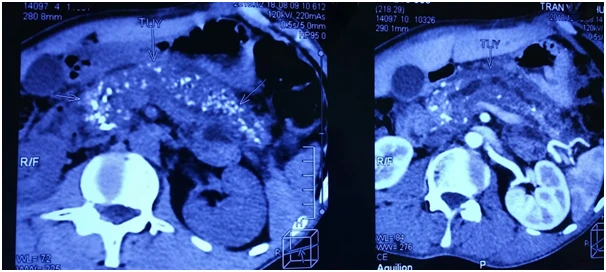

Hình chụp cắt lớp vi tính cho thấy hình ảnh viêm tụy mạn, sỏi ống tụy vùng đầu tụy, vôi hóa toàn bộ tuyến tụy. Ảnh: BVCC

Gần đây, bệnh nhân đã nhập BV Hoàn Mỹ Sài Gòn điều trị. Kết quả làm các xét nghiệm máu, chụp cắt lớp vi tính cho thấy hình ảnh viêm tụy mạn, sỏi ống tụy vùng đầu tụy, vôi hóa toàn bộ tuyến tụy, ống tụy giãn 10 mm từ đầu tụy đến đuôi tụy.